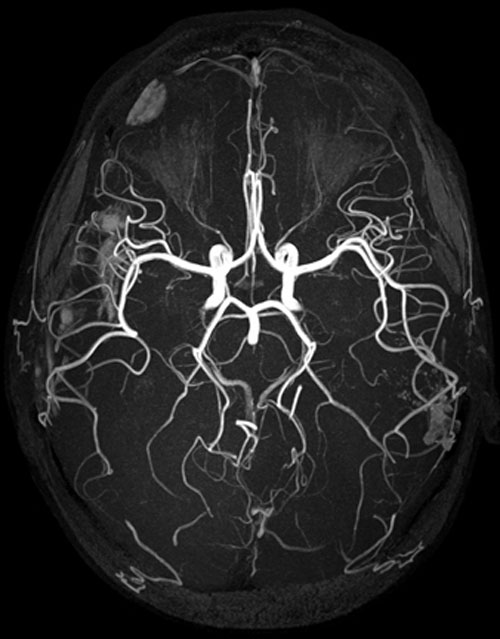

Attraverso una risonanza magnetica, i ricercatori hanno osservato che nei due gruppi di donne c’era un’attivita’ cerebrale diversa in reazione alla visione di immagini spaventose o minacciose. Le donne con depressione post partum hanno fatto registrare una risposta attenuata, nelle regioni del cervello responsabili della regolamentazione di empatia ed emozione rispetto a quelle sane. Questo risultato conferma quanto finora era noto, cioe’ che le madri depresse tendono ad essere meno in sintonia con le esigenze o i sentimenti dei loro bambini e meno sensibili, in generale, alle emozioni.

La risonanza ha rivelato anche una modalita’ diversa di coinvolgimento delle stesse aree cerebrali. Nelle madri depresse si sono evidenziate connessioni piu’ deboli tra le zone di regolazione delle emozioni, rispetto alle madri non depresse. Questo elemento, secondo i ricercatori, potrebbe far pensare ad un’origine biologica della depressione. Ma per indagare questo aspetto, secondo Eydie Mose’ Kolko saranno necessari altri studi. ”Ottenere informazioni piu’ dettagliate sulle cause e sui tipi di depressione post-partum – ha detto – puo’ portare a migliori cure e sulla base dei pattern neurali potremmo essere in grado di progettare terapie piu’ efficaci”.(ANSA).